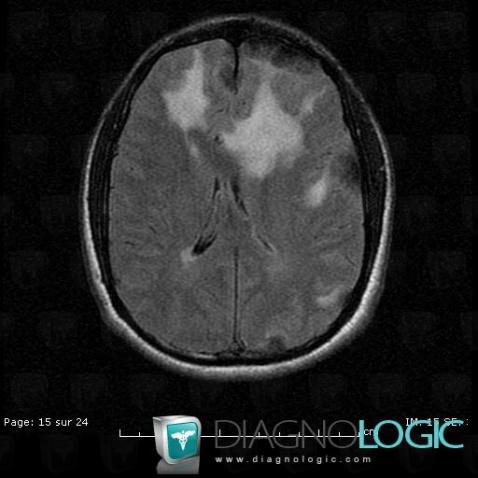

Langerhans cell histiocytosis, Cerebral hemispheres, MRI

Here is the specific information in the key image above:

- Diagnosis Langerhans cell histiocytosis, Location(s) Cerebral hemispheres, with gamuts Multifocal intracranial lesions